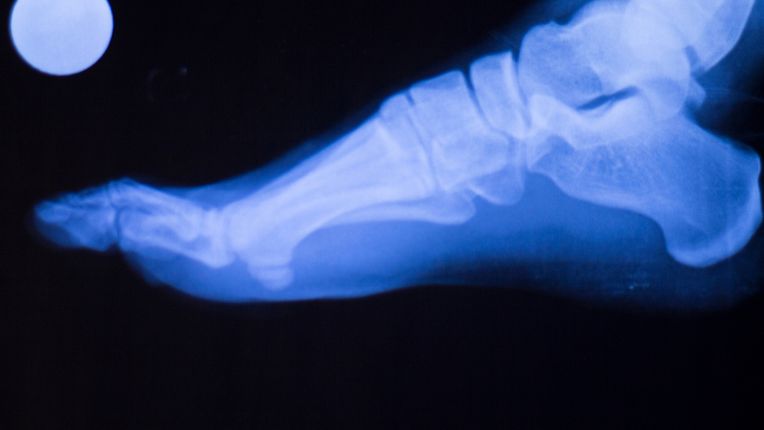

For foot surgery, you should see an orthopedic surgeon. Orthopedists treat all conditions that affect movement. Orthopedic surgeons treat and operate on pathologies of the legs, knees, feet, etc., deformities, traumas, fractures, etc. This specialty deals with bones, muscles, ligaments and tendons.

The practitioner can work on bone and joint restoration, etc. He can fit hip, knee and other prostheses, and perform hand and foot trauma surgery.

What conditions affect the foot? traumatology

Feet can be subject to many problems. What are some examples of foot problems ? These include stress fracture, percutaneous hallux valgus, neuroma, broken toe, clubfoot, etc.